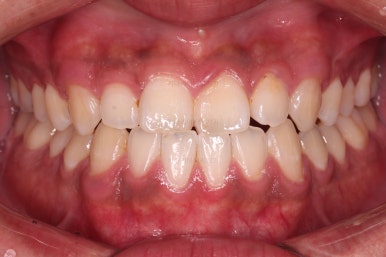

부산교정 장치를 부착했습니다.

이번에 선택하신 장치는 자가결찰 세라믹 장치에요. 스스로 철사를 묶는(결찰) 뚜껑이 달린(자가) 세라믹 성분의 장치인데요.

기능적으로도 우수하고, 세라믹이다 보니 미적으로도 장점이 있습니다.

이번 환자분은 엠파워 클리어라고 하는 장치를 사용했으며 흔히 아신느 클리피씨와 동일한 계열의 장치입니다.

장치 부착 직후의 느낌 참고해 주시고요.